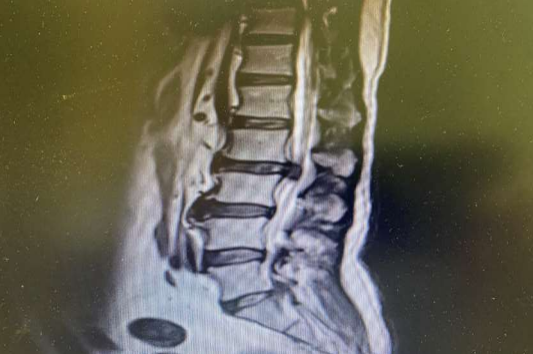

Emergent lumbar spinal magnetic resonance imaging (MRI) was obtained and revealed large extrude disc fragment at L2-3 level.

(Figure 1) with evidence of bilateral compression of L3 foramina

Figure 1

MRI proved to have a large extrude disc fragment at L2-3 level.

with evidence of bilateral compression of L3 foramina.